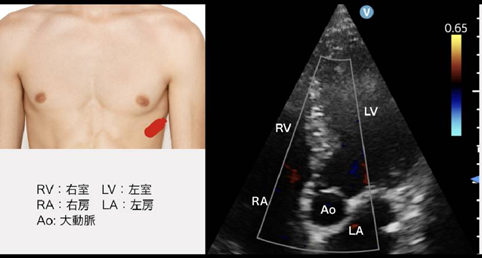

3.心尖部像の走査と正常像

(1) 心尖部4腔像

観察すること

【断層法】左室壁運動、LVEFの測定

【カラー】MR、e’

- 傍胸骨短軸像の心尖部レベルを指標に、 プローベを心尖部に固定し、 そこから胸壁側を見上げるようプローベを背側に倒すように傾ける。 あるいは傍胸骨長軸像から長軸方向にプローブを滑らせて、 心尖部三腔断面を描出、 そこから120°時計回りに回転させる

- 2つの手段があるが、 前者が難しい場合もあるため、 今回は後者を推奨する。

- 右房や左房が十分に観察できない場合は、 超音波ビームが、 より胸壁側に向かうようプローベを背側に傾ける. 逆に、 傾斜角度が強すぎた場合には、 右房や左房に加え大動脈弁も観察される

- 必ず心尖部の頂点にプローベが位置するように固定する。 そうすればその後の2腔像と3腔像の軸はぶれない。

- もしこの時点で描出不良の場合は、 体の傾きの角度をさらに倒すか、 緩めるかだけで、 心臓の位置が変わり描出できる場合がある。

- また、 呼吸の指示も重要で、 吸気ののちに呼気を指示し、 吐き切ったところで呼気止めをしてもらうと肺が被らずに描出できる場合がある。 人によっては吸気の終わりのほうが見やすこともあり、 横隔膜を上下させて心臓の位置を変え、 一番描出がしやすいところで息止めしてもらうのもよい。

▼確認事項

- 局所壁運動異常がないか確認する (後述)

- LVEF 50-65%

- ベッドサイドであれば見た目の判断 (visual LVEF)

- 心不全の場合、 LVEF 40%未満をHFrEF (heart failure with reduced ejection fraction)、 40%以上50%未満をHFmrEF (heart failure with mid-range ejectionfraction: HFmrEF) という

- LVEFの測定法にはいくつかあるが、 ベッドサイドですぐに計測は難しいため、 日頃からLVEFが計測されたエコー像と自身のVisual LVEFのズレがないかを確認しておくことが重要である。